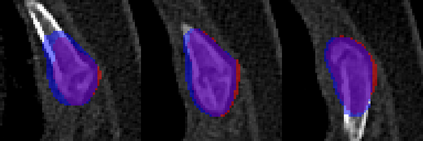

Rib fractures are a common and potentially severe injury that can be challenging and labor-intensive to detect in CT scans. While there have been efforts to address this field, the lack of large-scale annotated datasets and evaluation benchmarks has hindered the development and validation of deep learning algorithms. To address this issue, the RibFrac Challenge was introduced, providing a benchmark dataset of over 5,000 rib fractures from 660 CT scans, with voxel-level instance mask annotations and diagnosis labels for four clinical categories (buckle, nondisplaced, displaced, or segmental). The challenge includes two tracks: a detection (instance segmentation) track evaluated by an FROC-style metric and a classification track evaluated by an F1-style metric. During the MICCAI 2020 challenge period, 243 results were evaluated, and seven teams were invited to participate in the challenge summary. The analysis revealed that several top rib fracture detection solutions achieved performance comparable or even better than human experts. Nevertheless, the current rib fracture classification solutions are hardly clinically applicable, which can be an interesting area in the future. As an active benchmark and research resource, the data and online evaluation of the RibFrac Challenge are available at the challenge website. As an independent contribution, we have also extended our previous internal baseline by incorporating recent advancements in large-scale pretrained networks and point-based rib segmentation techniques. The resulting FracNet+ demonstrates competitive performance in rib fracture detection, which lays a foundation for further research and development in AI-assisted rib fracture detection and diagnosis.